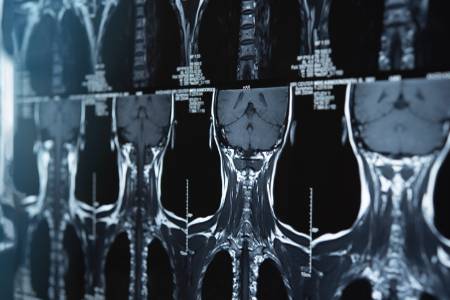

#. 40대 초반 A씨는 얼마 전 퇴근 후 급작스러운 두통으로 응급실을 찾았다가 신경과를 방문하라는 권유를 받았다. 신경과에 내원한 A씨는 MRI와 MRA 촬영, 혈액 검사 후 뇌혈관 협착 소견과 함께 고지혈증을 진단받았다. A씨는 이후 의사의 권유에 따라 뇌졸중 발생을 막기 위해 고지혈증 약물 복용과 식단 관리를 시작했다.

문하용 과장은 "MRI 및 MRA는 뇌경색을 비롯해 뇌동맥류, 뇌혈관 기형, 뇌종양 등 주요 뇌 질환 조기 진단에 큰 역할을 한다"며 "젊은 층의 경우 평상시 전조 증상을 느끼는 경우가 드문 만큼, 예방적 차원에서 정기 검진하면 이러한 리스크를 조기에 차단할 수 있다"고 설명했다. 뇌는 구조상 움직임이 없는 장기라 조영제 없이 MRA 검사를 할 수 있어 신체적 부담도 적은 편이다.